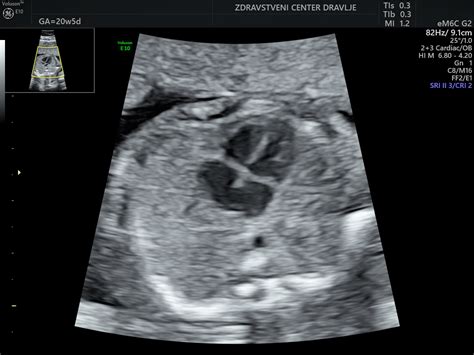

Če je dojenček obrnjen s hrbtom proti mamini hrbtenici (okcipitoposteriorna lega), je porod lahko težji, spremljajo ga močne bolečine v križu, porod ne napreduje optimalno in je pogosto potrebna zunanja pomoč. Položaj dojenčka lahko ugotovi ginekolog z ultrazvokom ali pa si pomagate z otipavanjem.